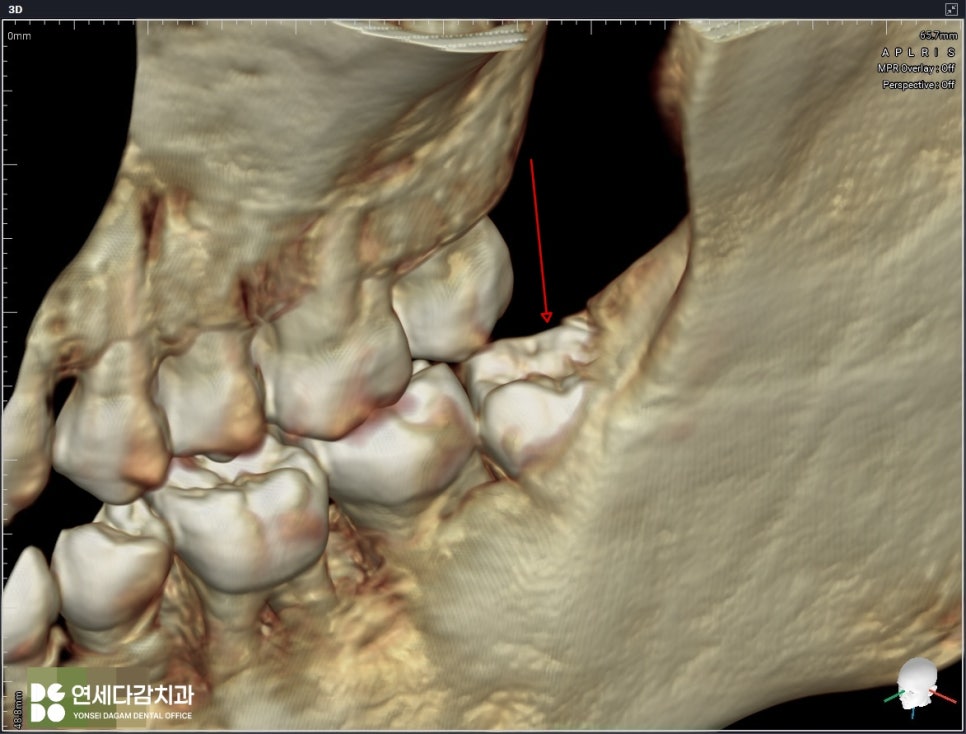

이는 2차원적인 엑스레이와는 다르게

입체적으로 치근단과 신경관의 관계를

시각화여 보여주는 장비입니다.

주행 경로를 정확히 파악할 수 있으며,

치아 뿌리의 각도와 방향까지 정확히 보여주어

발치 시 어떻게 분리해야 될지

어떤 방식으로 접근해야 되는지에 대한

섬세한 계획을 세울 수 있습니다.

해당 케이스는 신경관이 치근 끝에 닿아 있어

최소한의 자극으로 진행해야 됩니다.

특히 원심 부위는 잇몸 속에 묻혀 있으므로

절개 후 뼈를 정리하는 과정이 필요합니다.